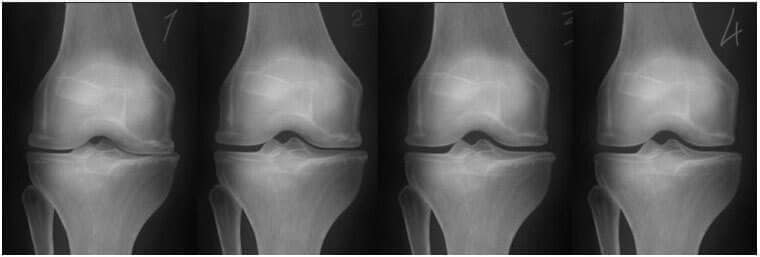

1. Nedostatak zajedničke prehrane. Tkiva niti su uništena.

2. Regeneracija tkiva zglobne hrskavice nakon dva tjedna korištenja "Nautubone".

3. Regeneracija tkiva zglobne hrskavice nakon 3 tjedna korištenja "Nautubone".

4. Zdrav zglob nakon završetka liječenja s Nautubone.

-Donja rendgenska slika prikazuje tipičan obrazac regeneracije zgloba koljena.